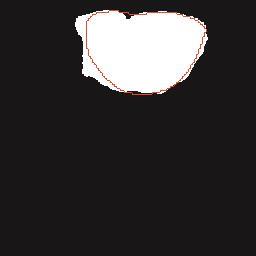

乳腺癌是全球女性最常见的恶性肿瘤之一,准确的病变分割对于乳腺癌的早期诊断与治疗具有重要意义。然而,由于病变形态的多样性以及超声成像机制的复杂性,现有基于深度学习的乳腺超声图像病变分割方法在分割准确性方面仍面临巨大挑战。为进一步提升乳腺超声图像中病变区域的分割精度,该文基于经典U-Net架构,提出了一种新型乳腺超声图像病变分割网络(CWSASKM-BBAM-Net)。首先,在网络中引入逐通道空间自适应选择核卷积模块(CWSASKM),根据不同通道的语义特征为每个空间位置自适应选择感受野大小,以增强多尺度信息的建模能力;然后,引入双向边界感知机制(BBAM),通过融合正向与反向注意力,对目标显著区域及其边界进行协同建模,同时逐步提升对非显著区域与病变区域的区分能力,以进一步强化边界信息的表达;最后,在3组公开乳腺超声图像数据集(BUSI、UDIAT和STU)上开展分割实验。结果表明:该方法在数据集BUSI上的杰卡德指数、精确率、召回率和Dice相似系数分别为71.97%、82.85%、81.40%和80.44%,较次优方法分别提升1.69、1.05、1.28和1.84个百分点;在数据集UDIAT上,这4项指标分别达到78.14%、88.31%、86.73%和86.10%,较次优方法分别提升了2.75、2.04、0.56和2.01个百分点;在外部数据集STU上,该方法也取得了优于其他方法的整体表现。实验结果表明,CWSASKM-BBAM-Net在乳腺超声图像分割任务中展现出更优的整体性能。